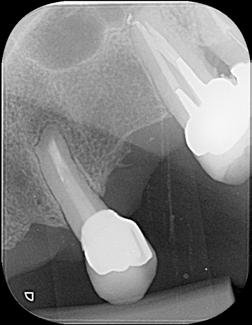

Paciente del género femenino, 44 años de edad, asistió al consultorio para realizar el retratamiento endodóntico del diente 22. Hemos hecho la radiografía inicial para evaluar el diente 22 y nos encontramos con una imagen radiolúcida en forma de globo, caracterizando una reabsorción radicular interna en el diente 21. Hemos hecho, entonces, una nueva radiografía para evaluar el diente 21 (Figura 1).

Figura 1 - Radiografia inicial

Durante la anamnesis la paciente relató haber sufrido un cabezazo del hijo hace dos años. El examen clínico reveló presencia de faceta de porcelana en el diente 21, prueba de sensibilidad pulpar positiva, ausencia de sintomatología y ausencia de alteraciones en la mucosa gingival. Solicitamos una tomografía computarizada cone beam (Figuras 2, 3 y 4) para confirmar el diagnóstico, evaluar si la reabsorción era comunicante o no y para estudiar la estructura dental radicular remanente.